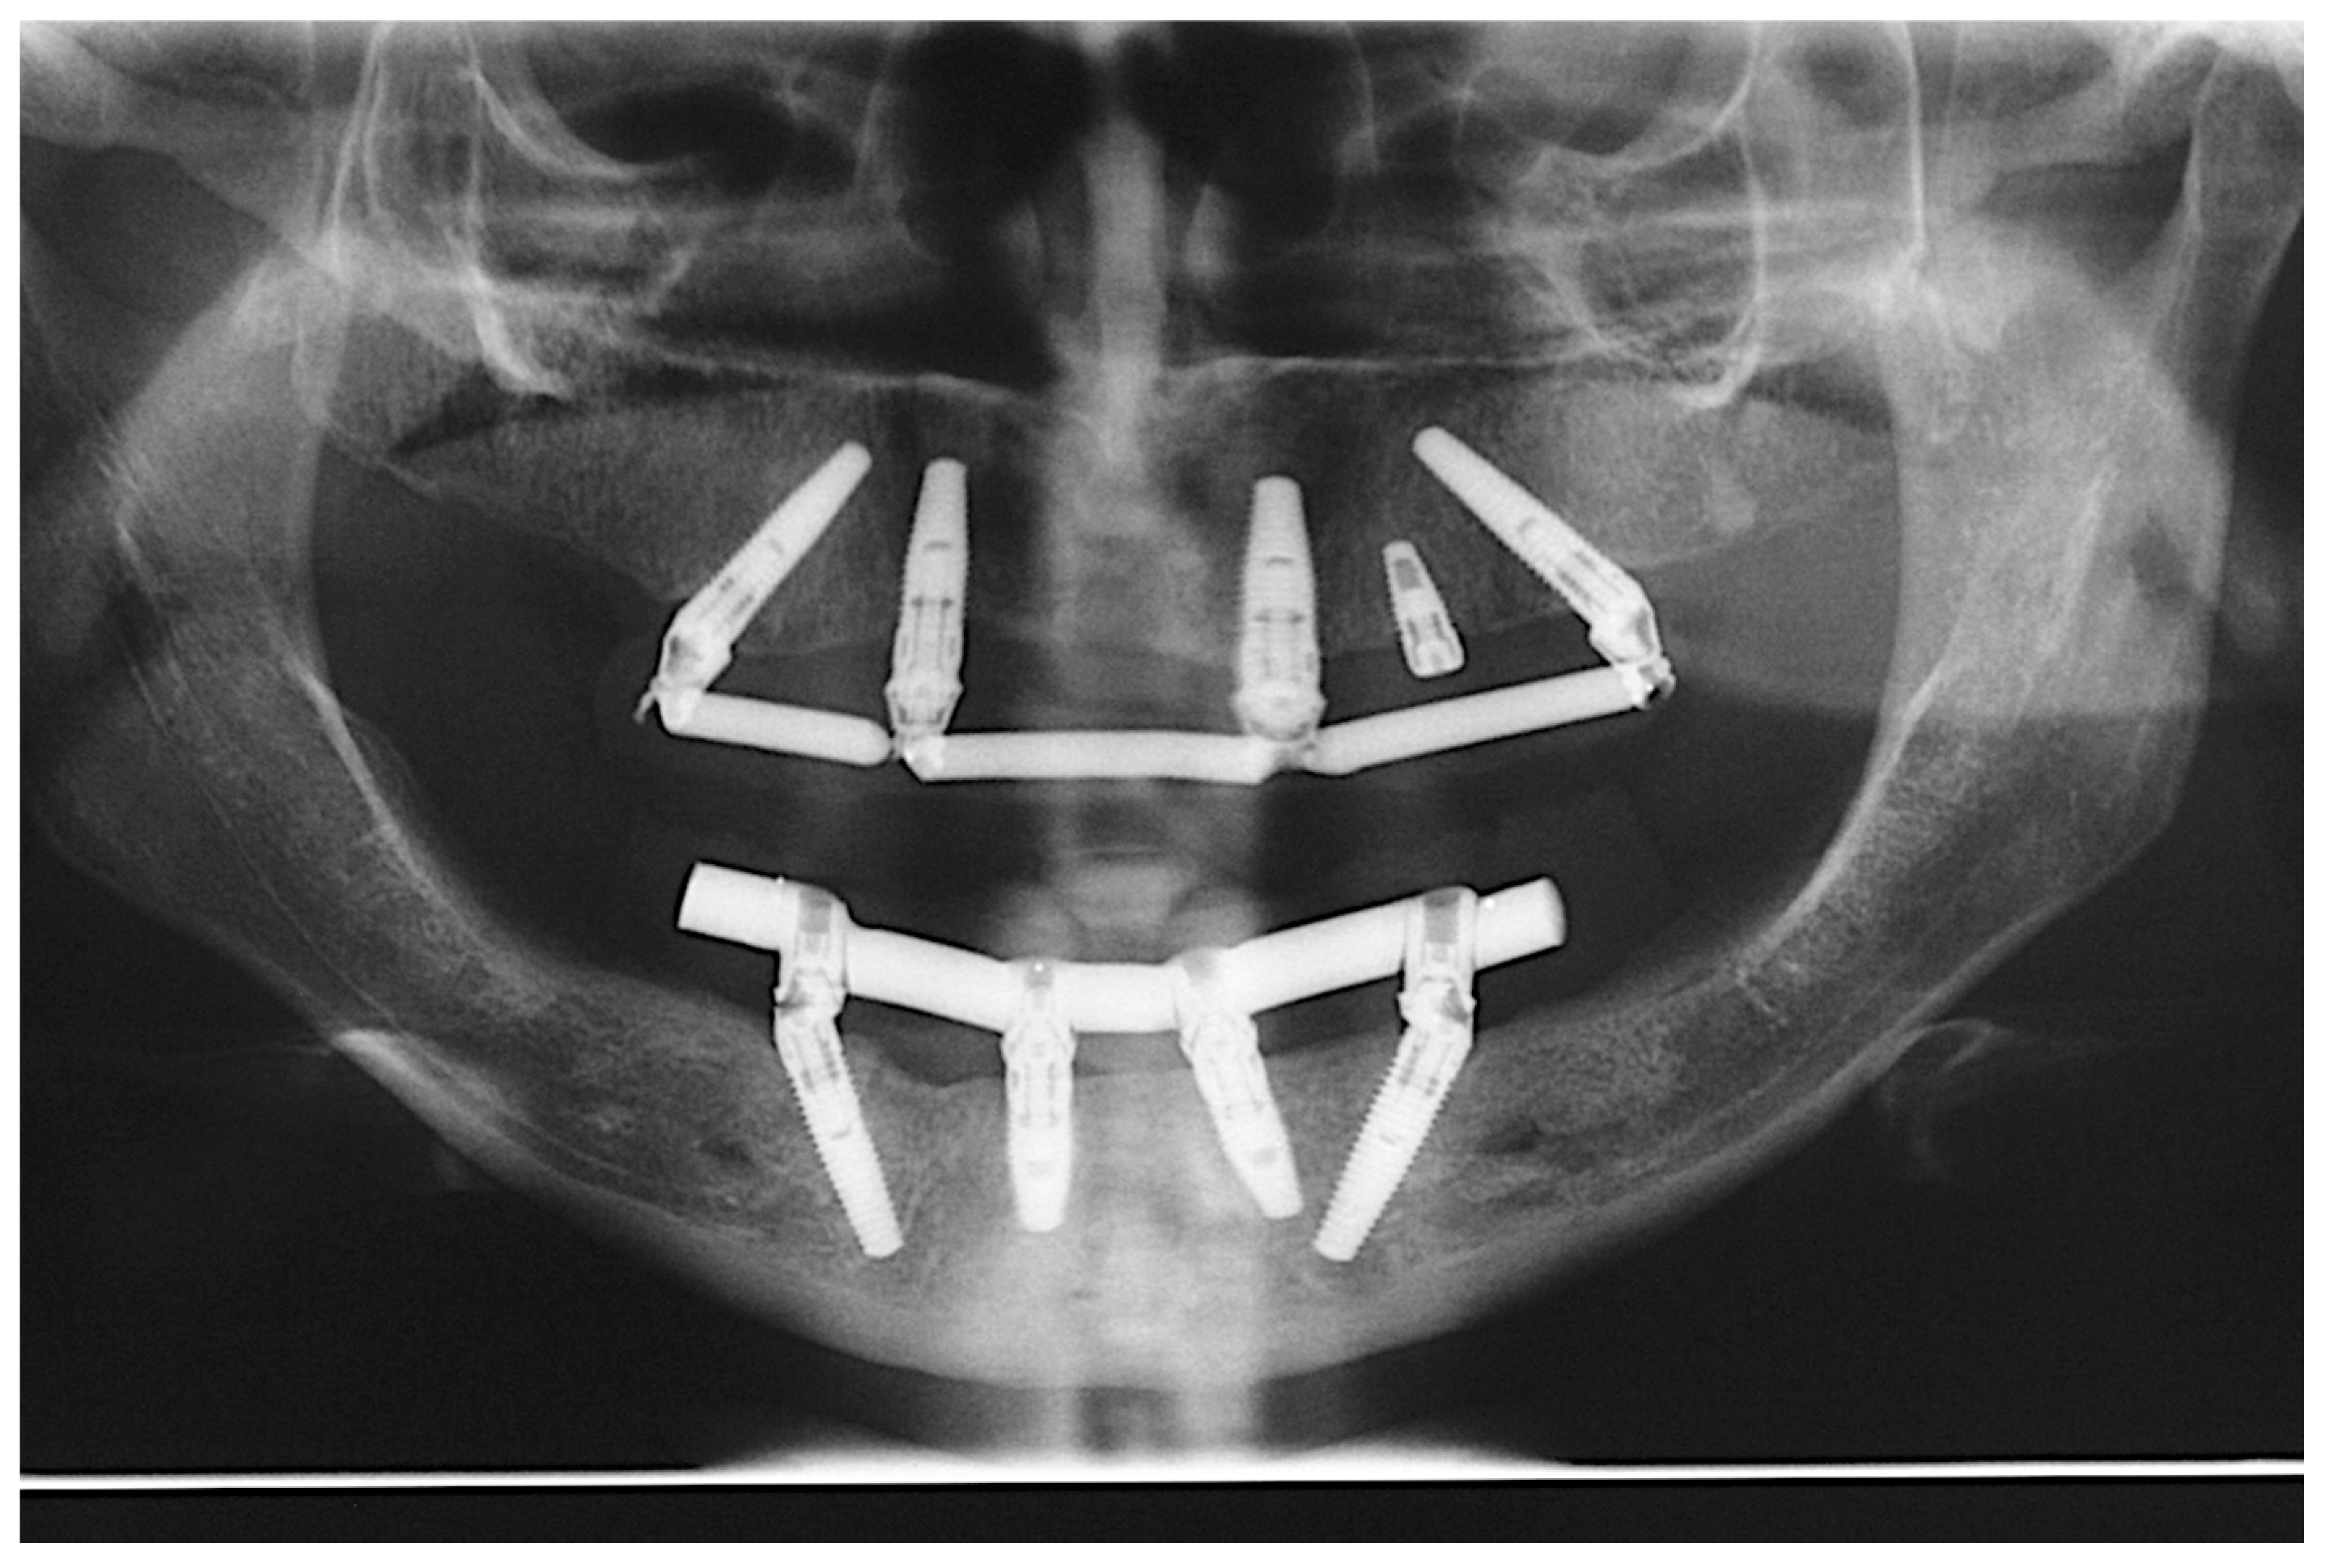

Patients were followed up for two years after implant installation, according to the following appointment schedules: time intervals of 7 days, 60 days, 6 months, 12 months, 18 months and 24 months [21]. The success criteria used in this study were, as suggested by Misch [23], no mobility, no pain during function, less than 2 mm of radiographic bone loss after initial surgery and no history of exudates. The clinical parameters of the implants were assessed during all follow-up appointments. Patients were examined using periodontal probing, CT scans, radiographs (Figure 13), intra- and extra-oral photographs and ISQ assessment.

Figure 13.

Two-year follow-up control panoramic radiograph.

All patients were instructed twice daily to use interdental brushes, dental floss and an oral hygiene system based on high-pressure water spray for biofilm control. Professional control was performed at every follow-up appointment [21]. Panoramic radiographs and CT scans were obtained before and after surgery and at every follow-up appointment. Inspection during the follow-up appointments included assessment of oral hygiene, soft tissue health (peri-implant pockets, pain and exudation), radiographic and tomographic aspects of the bone/implant interface, ISQ measurements, verification of screw loosening and other possible complications.